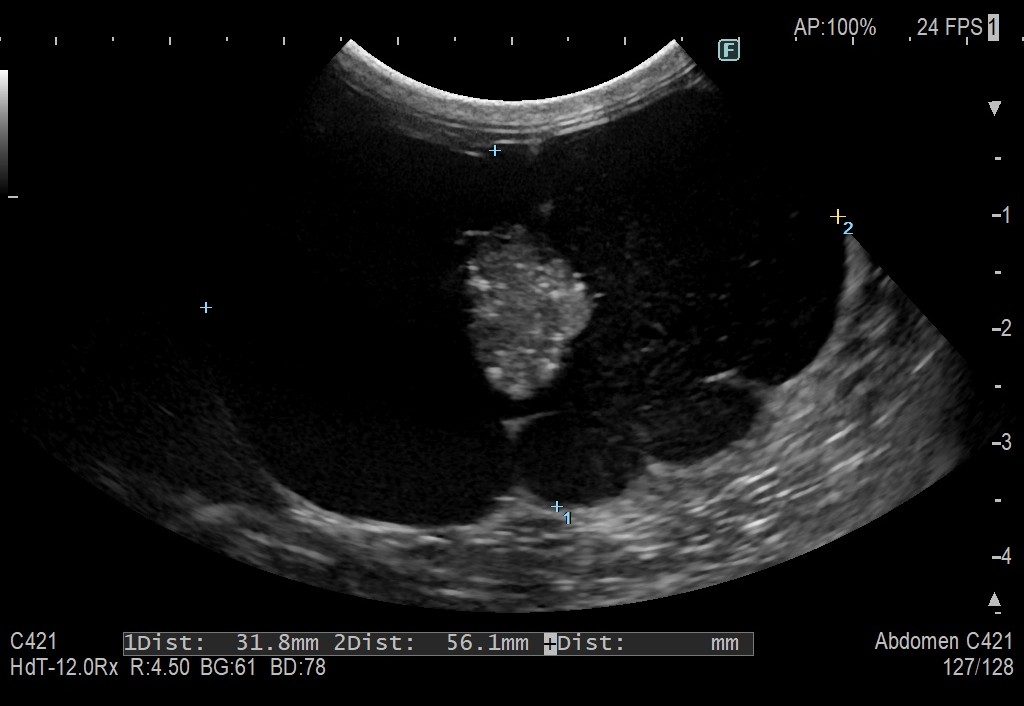

エコー検査にて右の腎臓に50mm大の嚢胞が発見されました。

CT画像でも右腎嚢胞は巨大であり、腎臓の正常な構造は消失していました。